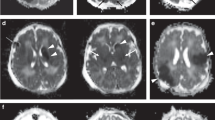

Arterial spin labeling (ASL) magnetic resonance imaging (MRI) can evaluate brain perfusion in neonates noninvasively. The aim of this study was to investigate whether ASL MRI can demonstrate perfusion abnormalities in neonates diagnosed with perinatal arterial ischemic stroke (PAIS).

Pulsed ASL perfusion MR images were acquired in the subacute stage (5–6 d after birth) and at follow-up (13 d to 16 wk after birth) in four PAIS patients. Images were visually evaluated for hypo- and hyperperfusion. In addition, cerebral oxygenation was monitored using near infrared spectroscopy (NIRS).

In three PAIS patients, ASL images showed hypoperfusion in the stroke area. In one of these, hyperperfusion was visualized in the periphery of the stroke area. In one PAIS patient, hyperperfusion was seen in the stroke area. In all infants, cerebral oxygenation was higher in the infarcted hemisphere as compared with the contralateral hemisphere. Follow-up ASL images showed partial recovery of perfusion in the stroke area.

ASL perfusion MRI is able to reliably detect hypo- and hyperperfusion in PAIS patients and can be used to monitor the evolution of perfusion after an ischemic event.